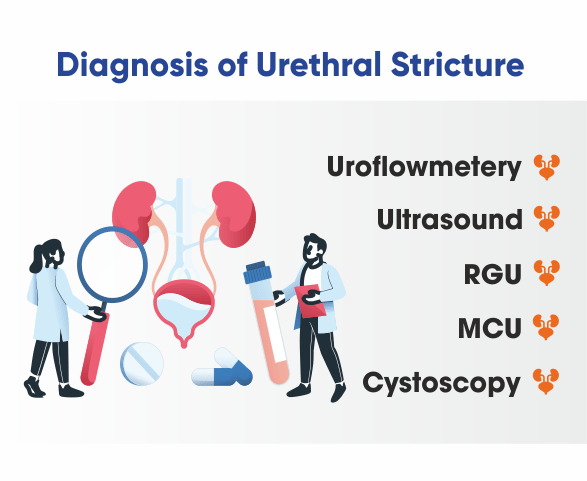

Diagnosis of Urethral Stricture

🔹 Urine Flow Test (Uroflowmetry) – Measures the speed and volume of urine flow.

🔹 Cystoscopy – A thin tube with a camera is inserted into the urethra to visually identify the stricture.

🔹 Retrograde Urethrogram (RUG) – An X-ray with contrast dye to locate and assess the severity of the stricture.

🔹 Ultrasound – Helps detect complications in the bladder or kidneys related to urinary obstruction.